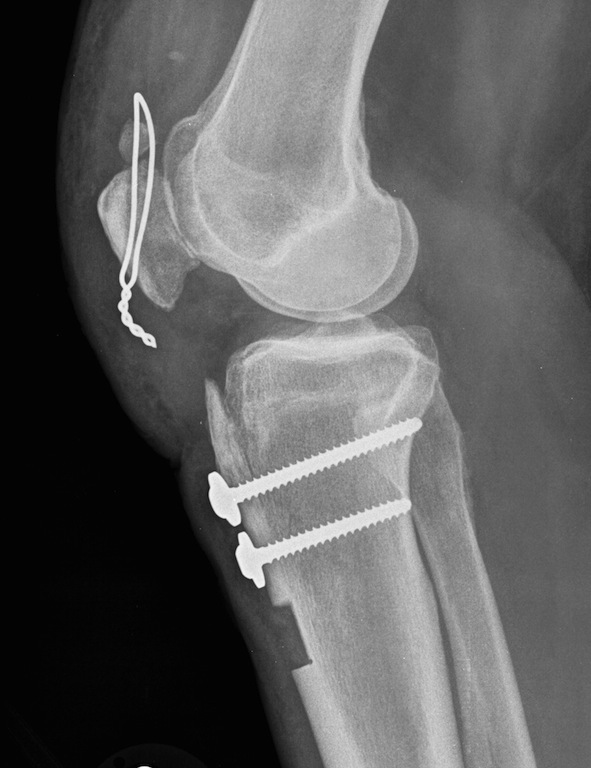

Tibial tubercle osteotomy and proximalization

Proximalization fo the tibial tuberosity